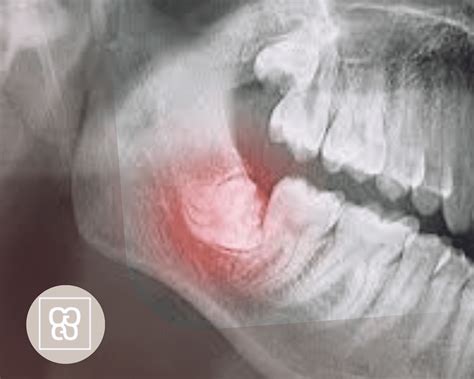

Extracción de muelas del juicio.

La extracción de las muelas del juicio implica un procedimiento quirúrgico con el fin de extraer una o más muelas ubicadas en las últimas posiciones de la boca, tanto en la parte superior como en la inferior. Cuando una muela del juicio no puede crecer adecuadamente debido a la falta de espacio, se le conoce como muela del juicio retenida, y puede ocasionar dolor, infección u otros problemas dentales. No extraerla cuando sea necesario puede conllevar varios riesgos y complicaciones.

En ocasiones estos molares se desarrollan bien y brotan sin problemas. Pero hay casos en los que no tienen suficiente espacio, esto causa que queden retenidas o salgan solo de forma parcial. En este último caso puede ocurrir que crezca en ángulo hacia el segundo molar o hacia atrás; o que esté derecha, pero atrapada en el maxilar.